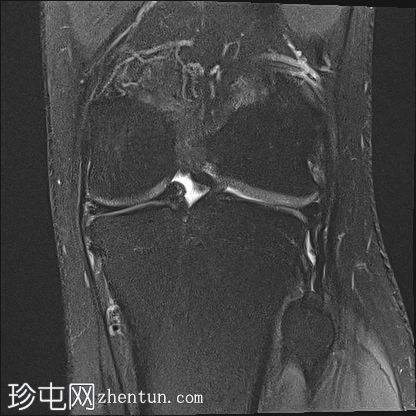

2.jpg

冠状面PD

脂肪饱和度

股骨内侧髁发育不全

胫骨髁间棘发育不全

腓骨头发育不全

前交叉韧带(ACL)和后交叉韧带(PCL)发育不全

髌腱延长,低位插入。

腘绳肌腱起源异常

外侧胫骨半月板韧带增厚;与外侧韧带(LCL)连接

术后可能出现股四头肌腱改变

本病例展示了腓骨半肢畸形(I型)的特征性表现。然而,腓骨半肢畸形可能伴有多种其他异常及异常组合,包括本例中的十字韧带发育不良。本文所述结果仅代表该疾病的一种可能变体。